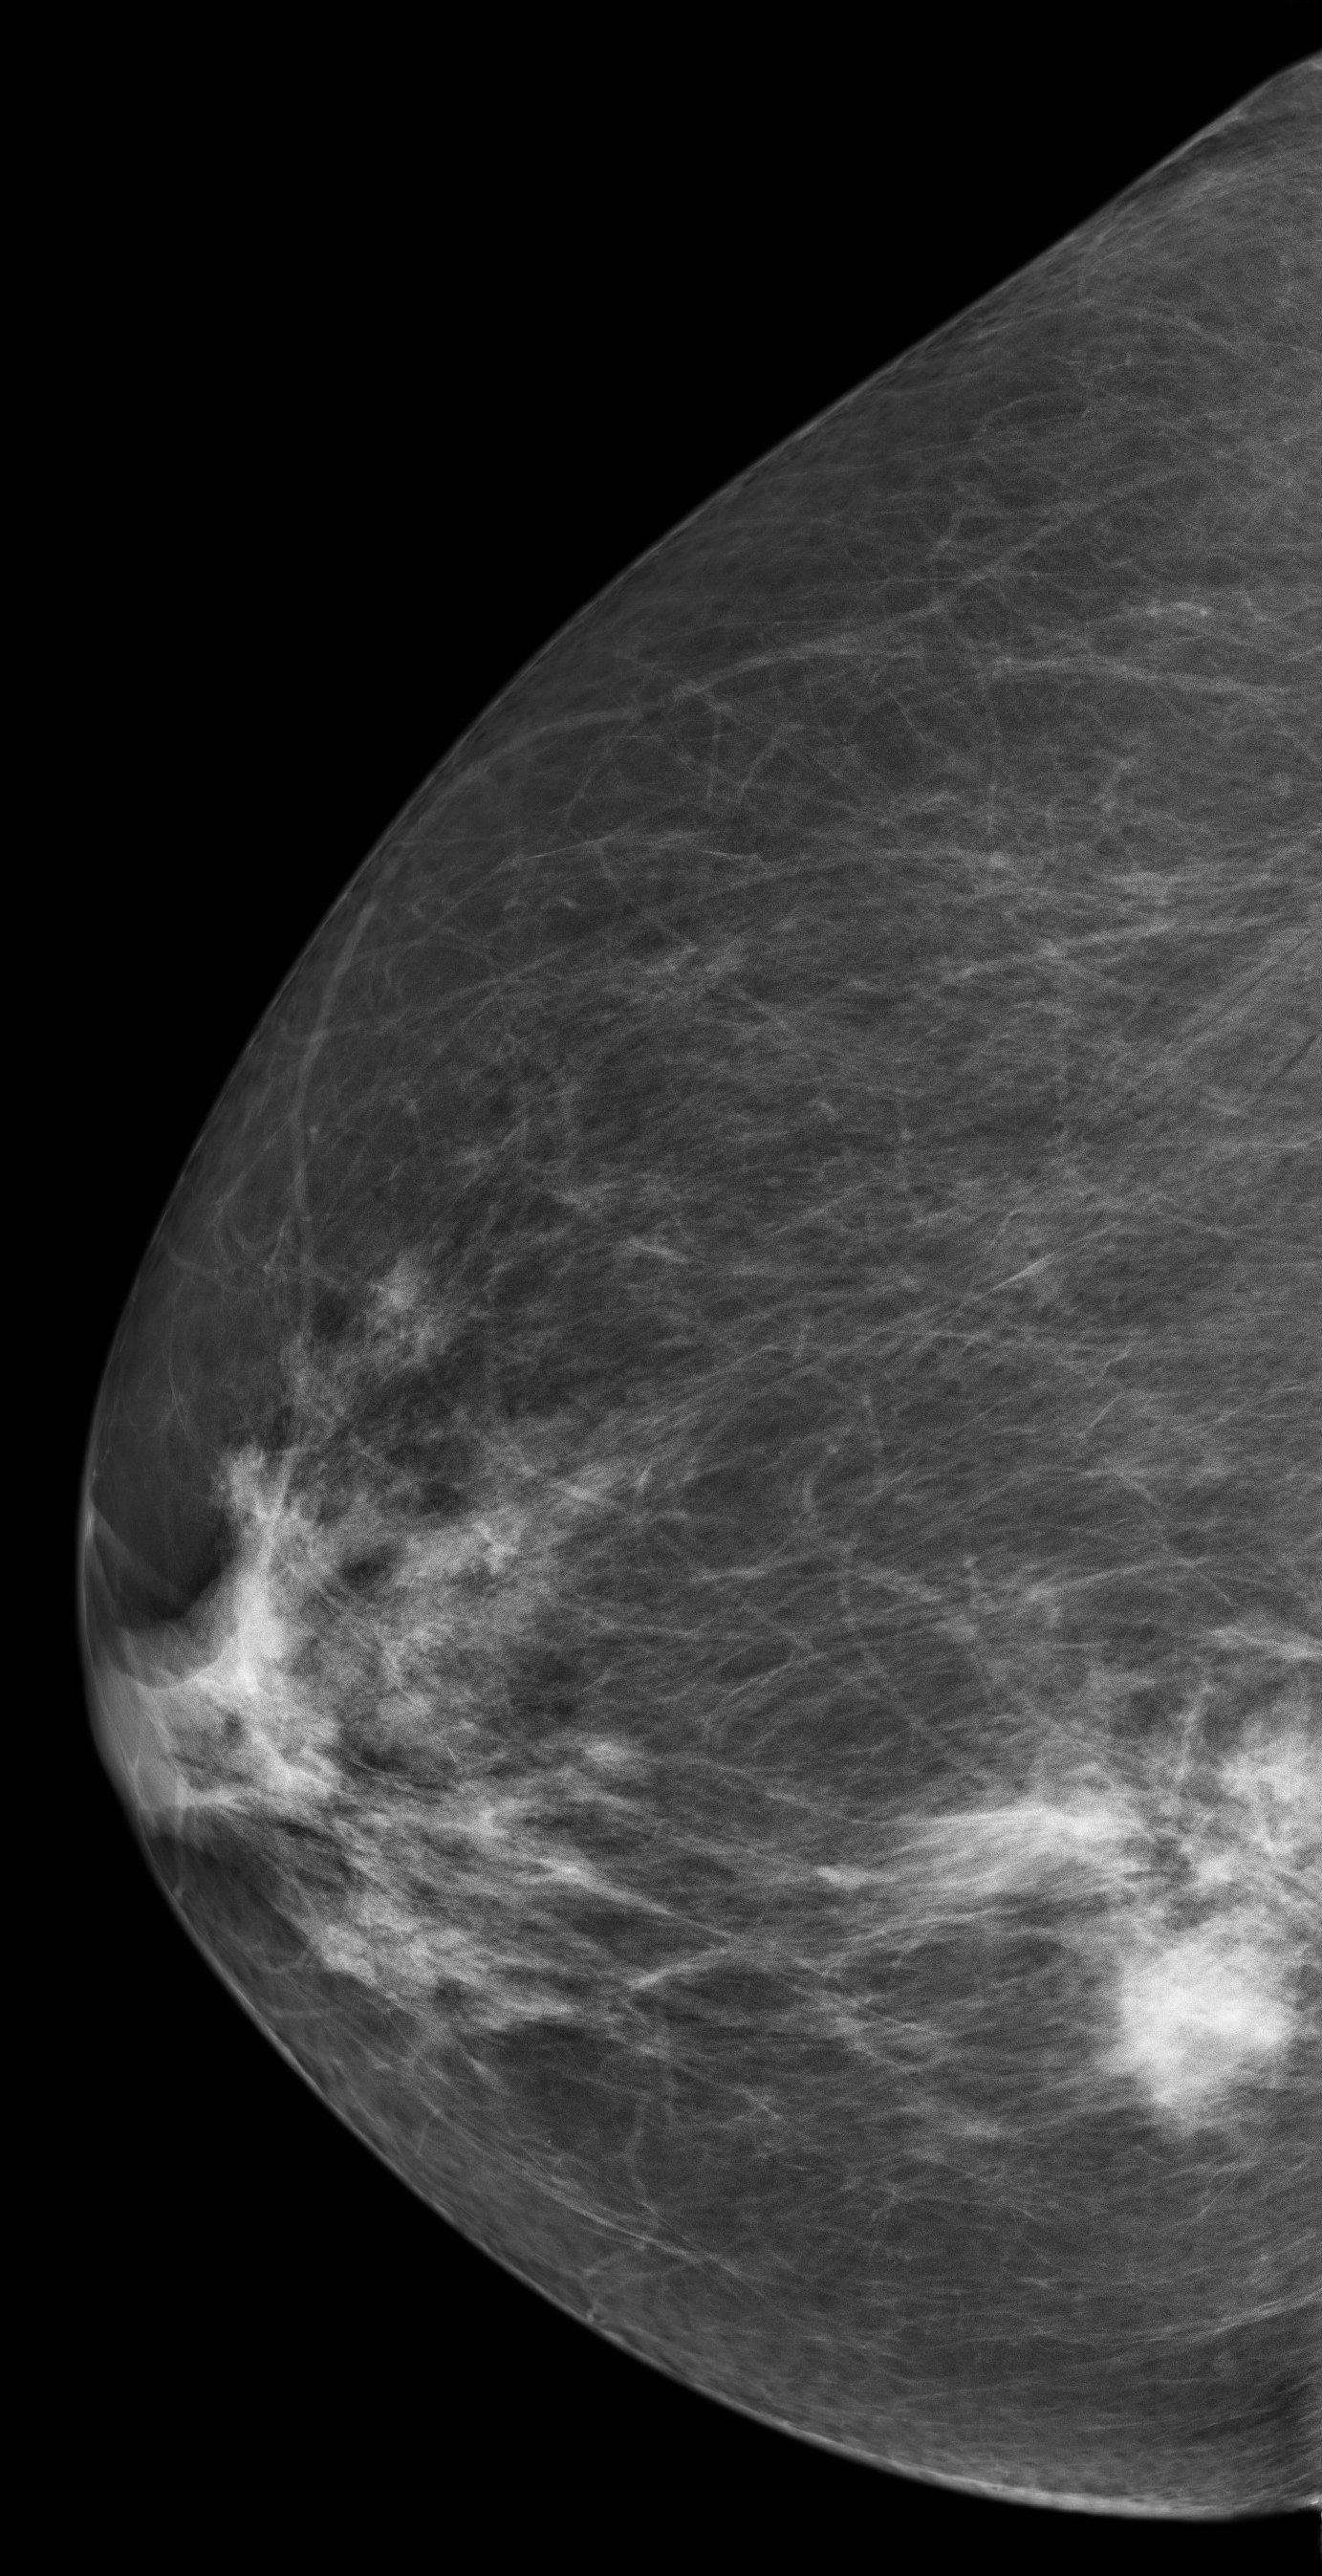

U ác tính

Ung thư biểu mô tiểu thùy vú (Lobular breast carcinoma)